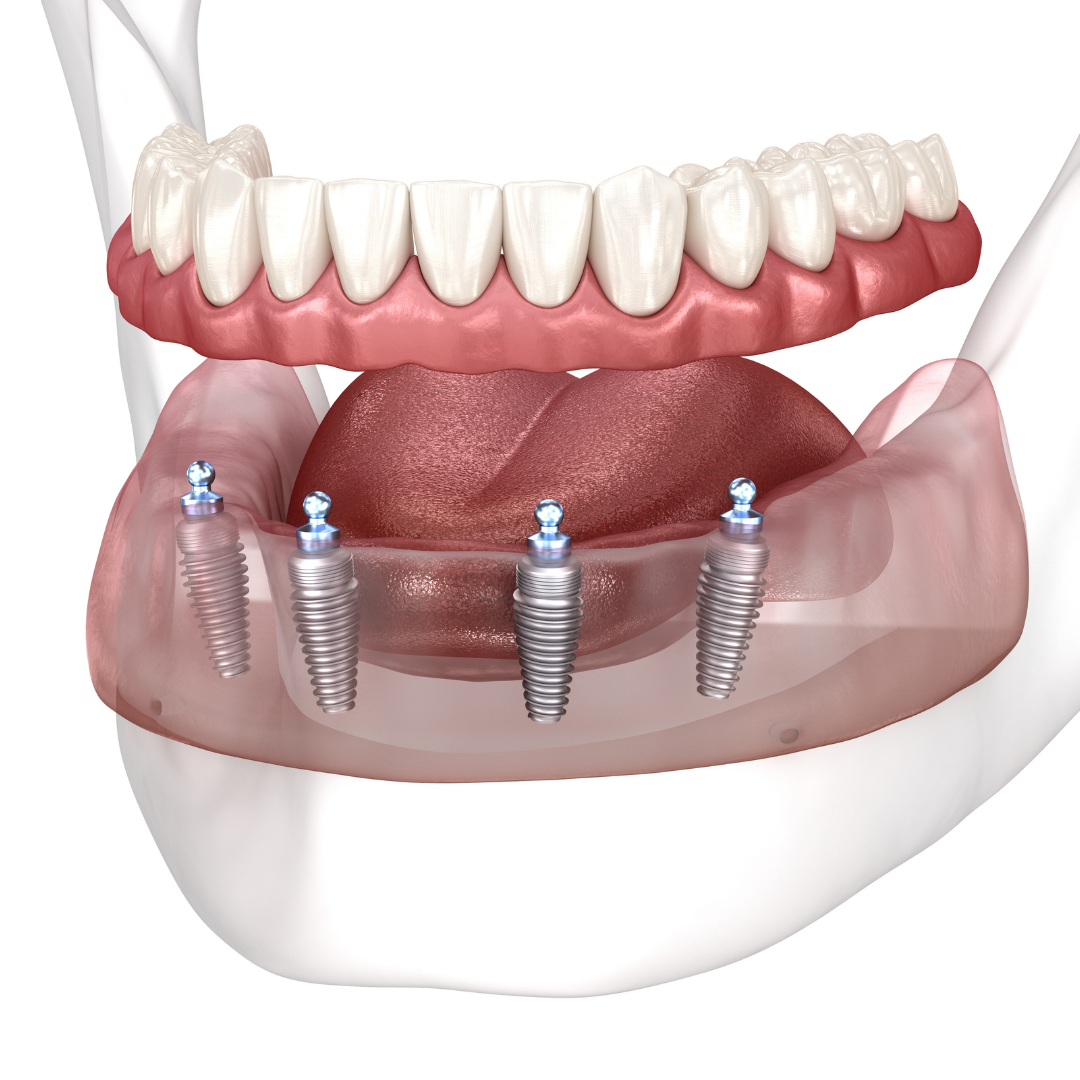

Every single dental implant consists of three parts - the implant, the abutment, & the crown. The implant is made of medical grade titanium. This part is surgically placed into the patient’s jaw bone and left to heal for 4-6 months afterwards.

This implant piece acts as the foundation for the rest of the tooth. Once the bone around the site has healed, the abutment and crown are placed on top of the implant. The end result is a beautiful, natural-looking new tooth!

Few people will ever be able to tell the difference between your implants and your real teeth.

Includes surgical placement of 4 implants.